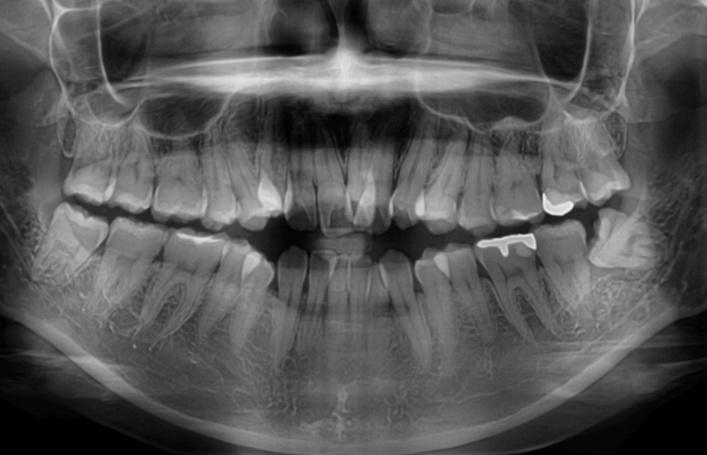

歯並びの乱れ(叢生)が気になる

| 年齢・性別 | – |

|---|---|

| 主訴 | 歯並びの乱れ(叢生)を気にされて来院された。咬み合わせや審美的な改善を希望されていました。 |

| 治療期間・回数 | 3年・28回 |

| 費用 | 840,000円 |